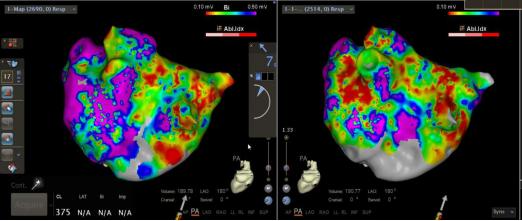

Marshall韧带化学消融这项技术,解决了导管消融术对于某些房颤病灶“到不了,消不透”的困难和瓶颈,提高了消融效率和手术成功率,能够使持续性房颤、左房房扑和复发性房颤消融的无事件生存率提高15%。首例Marshall韧带无水酒精消融的成功,代表我院心血管内科心律失常团队房颤消融技术达到国内领先水平。该技术的成功开展将会进一步提高房颤的治愈率,给我省房颤患者带来福音。

进行Marshall韧带消融后,基质标测提示左房嵴部和部分二尖瓣峡部区域电位消失